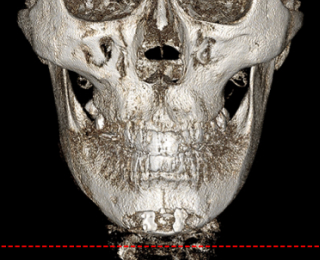

• 신경 보존 절골법 이미지

무분별한 절골은 감각 이상과 같은

심각한 후유증을 남길 수 있습니다

신경 손상을 최소화하여

안전을 최우선으로 합니다

수술 전 3D-CT를 통해 신경의 위치를

1mm까지 분석하고,

원장님이 직접 수술 경로를 디자인하여

신경 손상을 원천 차단합니다

* 수술전 원장님이 직접 디자인한 사진입니다